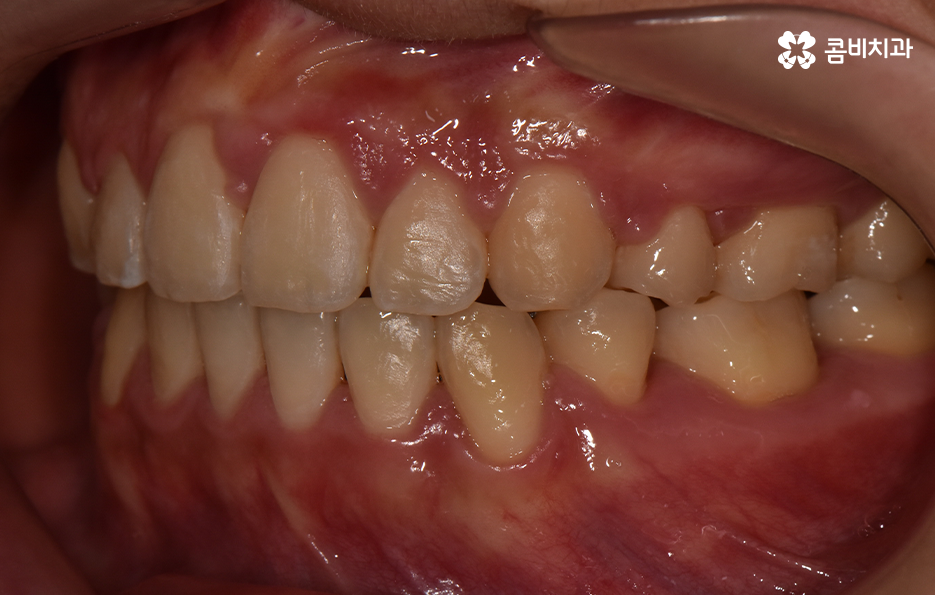

이처럼 치열의 변화는 얼굴형 변화에도 많은 영향을 줄 수 있기 때문에 치아교정의 만족도는 치열뿐 아니라 환자 개개인의 골격과 얼굴형을 고려하여 잘 어울리는 조화적인 측면과 치아의 건강 등 고려해야 할 점이 많다는 것을 알 수 있는데요

보통 치아교정을 통해 눈에 띄게 얼굴 변화를 느끼게 되는 경우는 쉽게 말해 발치를 통한 교정으로 볼 수 있어요. 그 이유는 치아를 발치하게 되면 발치한 만큼의 공간이 악궁에서 축소가 되기 때문에 그로 인해 얼굴라인이 갸름하게 변하게 되거나 돌출입발치교정 같이 돌출입의 개선이 되는 거예요

치아를 발치하고 이동하면서 얼굴 변화의 대표적 사례는 돌출입 개선이나 얼굴 라인의 변화뿐 아니라 얼굴 비대칭의 개선이나 팔자주름이 옅어지는 등의 변화를 꼽을 수 있어요